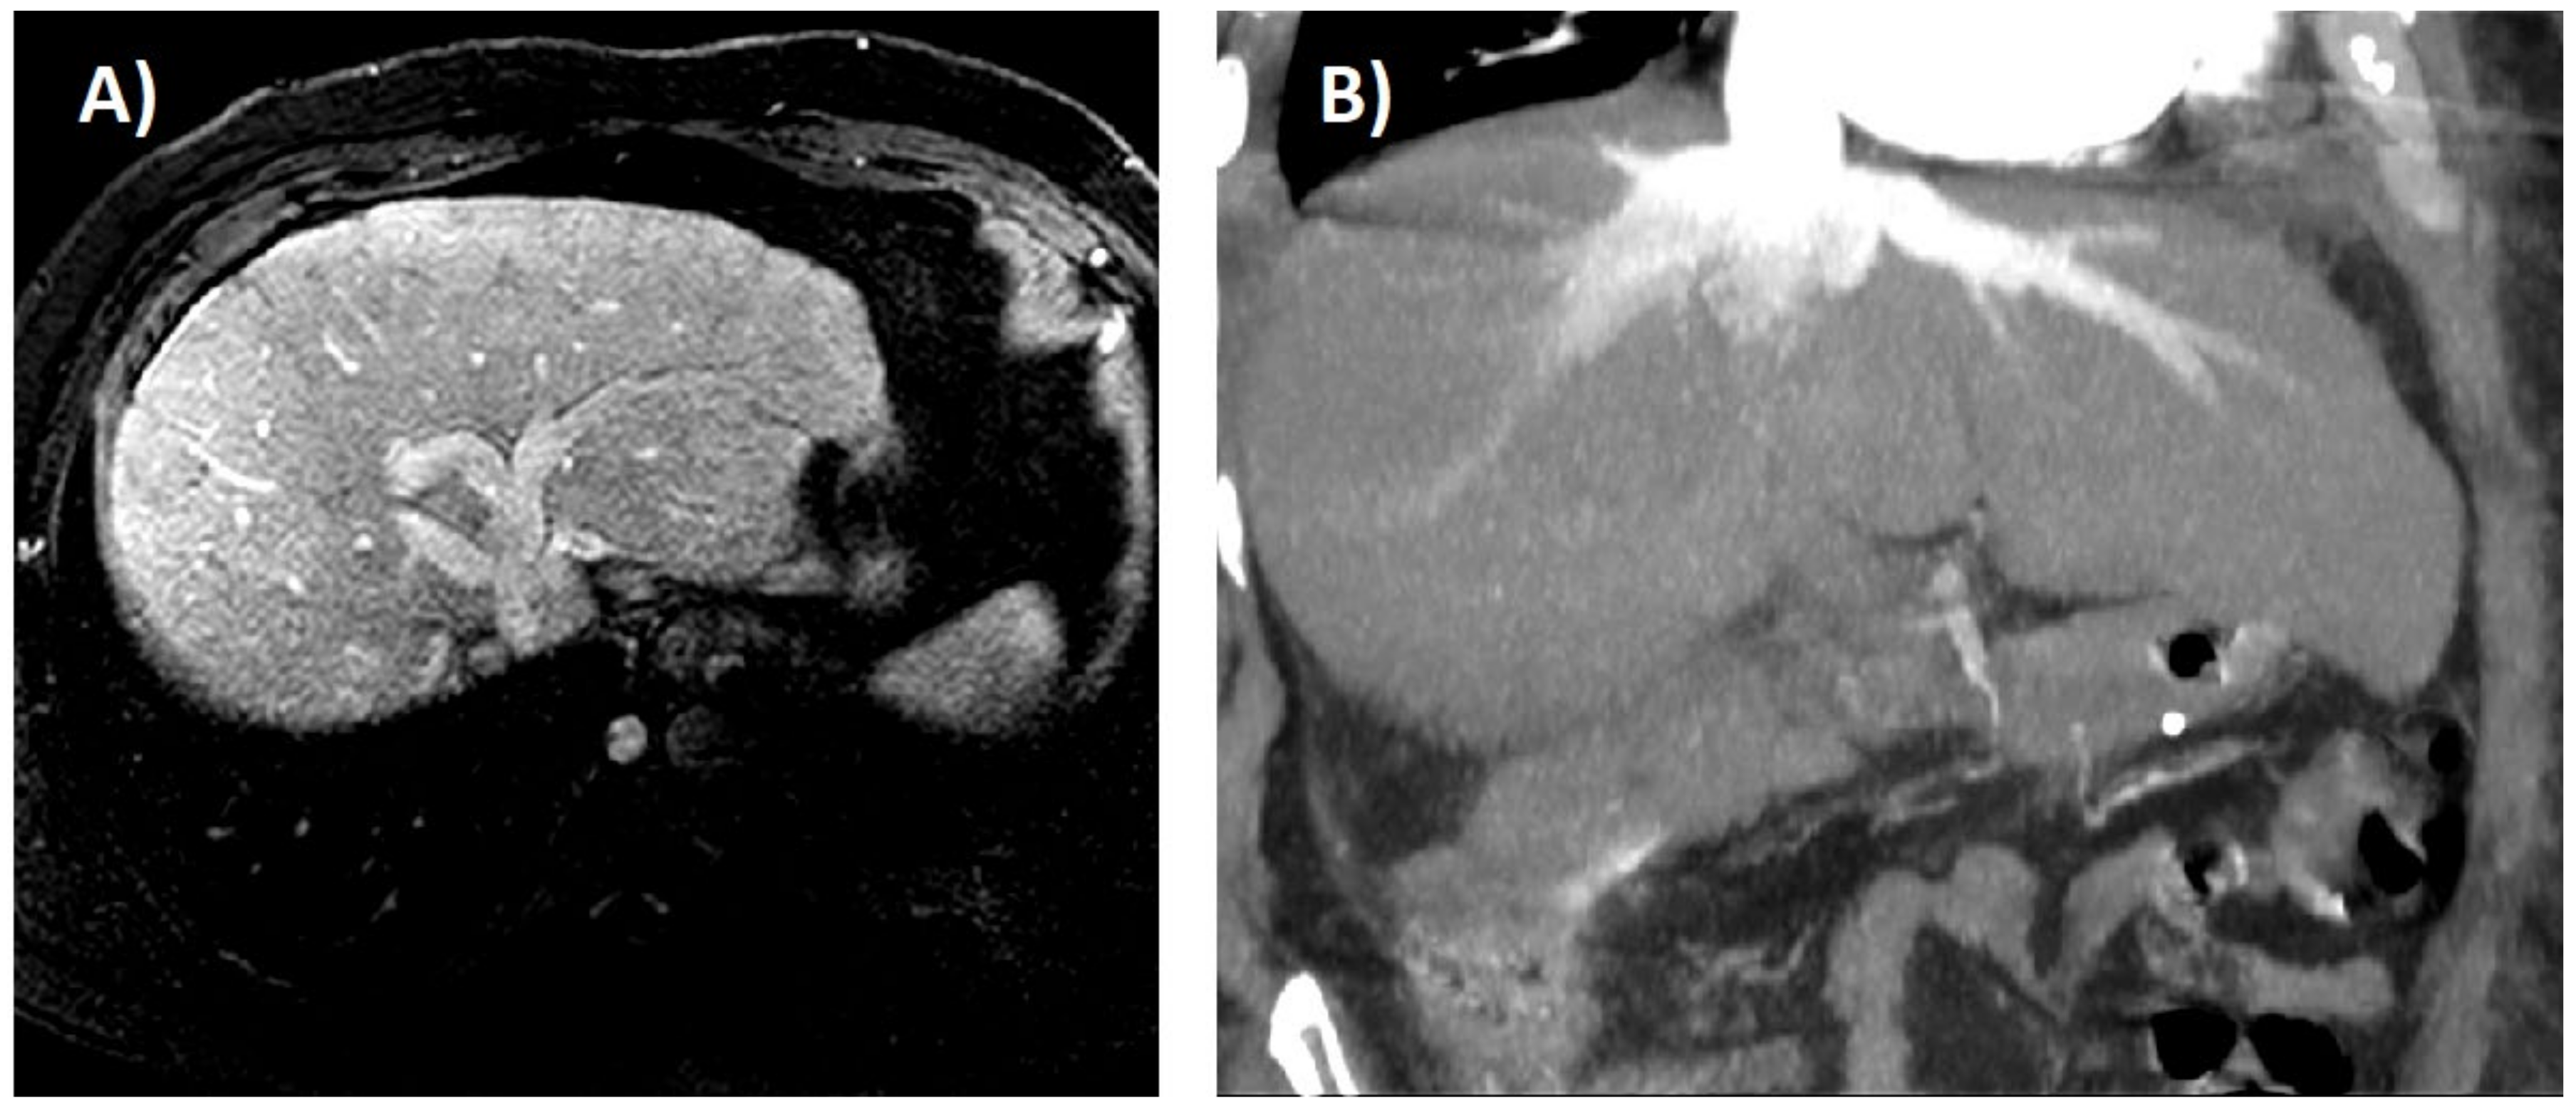

6. Imaging Tests

- Morales, A.; Hirsch, M.; Schneider, D.; González, D. Congestive hepatopathy: The role of the radiologist in the diagnosis. Diagn. Interv. Radiol. 2020. [Google Scholar] [CrossRef] [PubMed]

- Wells, M.L.; Venkatesh, S.K. Congestive hepatopathy. Abdom. Radiol. 2018, 43, 2037–2051. [Google Scholar] [CrossRef] [PubMed]